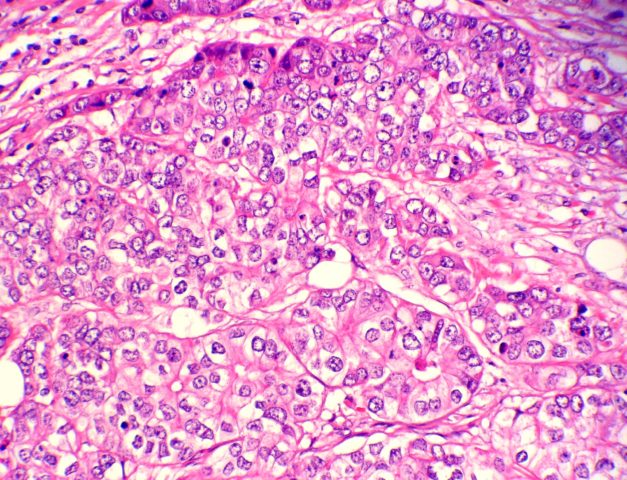

Si definisce tumore mammario triple-negative un gruppo di neoplasie le cui cellule mammarie non esprimono i recettori degli estrogeni e del progesterone (ER e PR) e non esprimono eccessivamente HER2. Solitamente, rapportandoli ad esempio ai tumori dovuti ad iperproduzione di estrogeni, quelli triple-negative mostrano una maggiore aggressività con un più elevato tasso di proliferazione cellulare neoplastica. Mediante dei profiling genetici precedenti si era già notato che si aveva prognosi peggiore nelle giovani donne colpite da questo tumore e che le pazienti più anziane mostravano molto biomarkers come le citocheratine e Bcl-2, nota proteina coinvolta nella morte cellulare programmata con effetto solitamente anti-apoptotico.

Il problema principale dell’assenza di ER, PR e HER2 è l’impossibilità di applicare dei trattamenti terapeutici che possano confliggere col pathway di trasduzione del segnale degli ormoni (ad esempio, nei tumori che esprimono ER sono usati agenti farmaceutici come il tamoxifen, uno dei primi ad essere stati applicati nella terapia oncologica del tumore al seno). In generale, per quanto riguarda i dati di incidenza nella popolazione, si è osservata una prevalenza nelle donne giovani (<50 anni), nelle donne di etnia afroamericana e ispanica, e nelle donne con mutazioni genetiche di BRCA1.